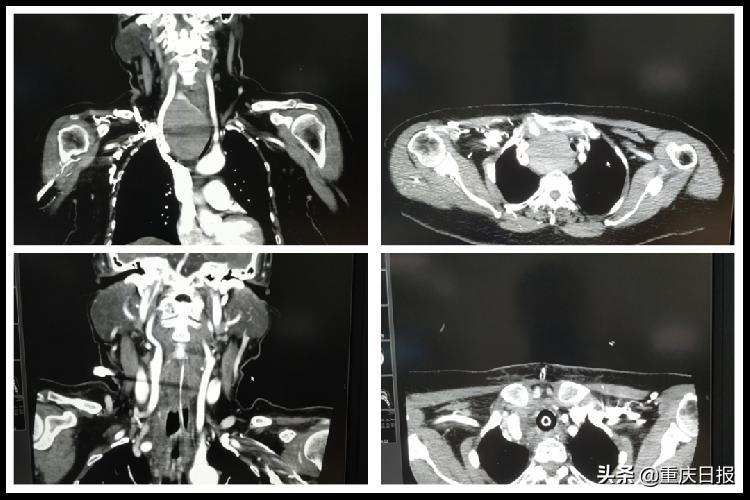

▲图为患者术前、术后CT检查。陆军特*医色**学中心供图

30年前,张先生被查出“甲状腺巨大肿瘤”,因肿瘤大部分位于胸骨后,从未有过不适感,张先生没有重视,未行特殊治疗。今年5月,张先生因咽喉部不适入住中心耳鼻喉科,没想到30年的甲状腺肿瘤内部突发出血,肿瘤体积急剧增大导致压迫气管,张先生忽然声音嘶哑、呼吸困难,随时可能窒息死亡,情况十分危急。

麻醉成功建立后,手术正式开始。高博手持钨针电刀,在本科室黄琦医师及耳鼻喉科余小平医师的配合下,逐层切开张先生颈部皮肤、皮下脂肪……经过3个多小时的努力,手术团队在不开胸的条件下,经过相对局促的颈部横切口,成功将张先生胸骨后约8*7cm大小的巨大甲状腺肿瘤完整切除。